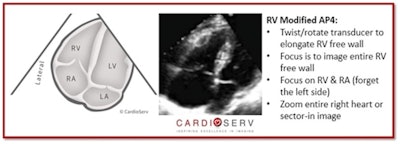

In its updated guideline, the ASE explained that there are three different scanning views that can be obtained from the apical 4 (AP4) window to properly evaluate the RV and RA:

- RV-modified AP4 view

Please note that the purpose of the RV modified AP4 view is to qualitatively evaluate RV function; quantitative methods should not be measured in this view.